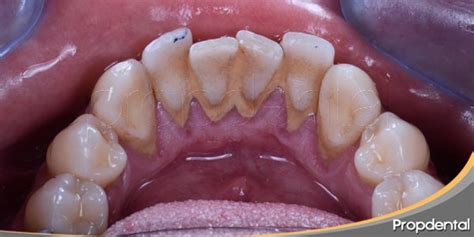

Cuando se cae un trozo de sarro dental, suele indicar acumulación crónica de placa calcificada. Aunque puede parecer un alivio, su caída puede dejar expuesta la encía o una caries. Entendamos qué es el sarro: es esa placa bacteriana que, por falta de higiene adecuada, se endurece y calcifica sobre los dientes (también llamado tártaro dental o cálculo dental). Suele tener un color amarillento o marrón y una textura rugosa. El sarro se adhiere fuertemente al esmalte y no se desprende fácilmente por sí solo con el cepillado normal.

- Acumulación excesiva: Cuando el sarro lleva mucho tiempo acumulándose, puede formar depósitos grandes en tus dientes. A veces, una parte de ese depósito puede fracturarse o despegarse, por ejemplo al masticar algo duro o simplemente por su propio volumen.

- Ubicación típica: El sarro tiende a formarse especialmente detrás de los dientes inferiores frontales (incisivos inferiores) y en las muelas superiores, porque ahí desembocan las glándulas salivares. La saliva contiene minerales que facilitan la calcificación de la placa. Por eso, no es raro que un “trozo de sarro” provenga de la parte interna de los dientes delanteros de abajo, que es justo donde más se acumula.

Técnicamente, el sarro generalmente no se cae por sí solo como resultado positivo; es decir, no esperes a que tu boca se “limpie sola”. Si notas que se caen fragmentos de sarro sin asistencia, suele ser porque la situación ya es prolongada y severa. Es más, cuando a alguien “se le cae el sarro solo”, muchas veces es porque ya hay cierta destrucción debajo (encía retraída, diente un poco flojo, etc.).